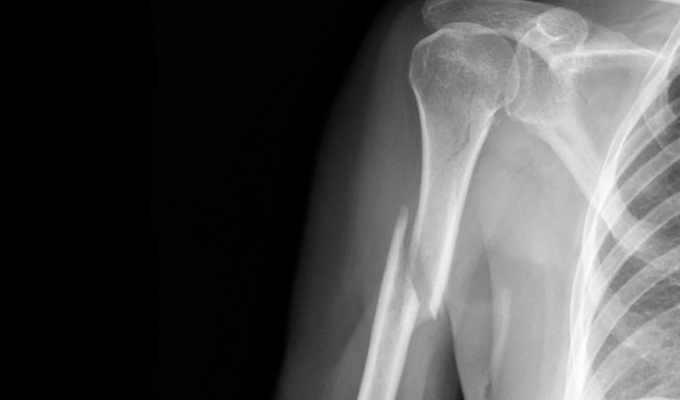

Патологические переломы плечевой кости могут быть:

- по локализации – диафизарные и внутрисуставные. Диафизарные переломы, в свою очередь, бывают проксимальных отделов кости (тех, которые ближе к плечевому суставу), средней части плеча, дистальных отделов (возникающих ближе к локтевому суставу);

- по степени поражения – неполные (в виде трещин костной ткани) и полные. Полные переломы, в свою очередь, бывают без смещения отломков кости и с их смещением;

- по нарушениям со стороны кожного покрова – закрытые (без ранения кожи) и открытые (с ее ранением);

- по наличию осложнений – неосложненные и осложненные.

Диафизарными называют те патологические переломы плечевой кости, при которых поражена любая локация фрагмента, расположенного между суставными концами плечевой кости.

Линия патологического перелома при данном повреждении очень вариабельна – равно как и ее протяженность. По некоторым особенностям такие переломы могут быть:

- с вдавливанием костных участков друг в друга;

- с формированием крупных трещин;

- со смещением коркового слоя соседних участков буквально друг на друга.

- рентгенография – при этом делают снимки в прямой, боковой, а при необходимости и в косых проекциях, обнаруживают линию перелома. Также в ряде случаев может быть выявлена патология, которая привела к развитию описываемого нарушения – в частности, опухоль;